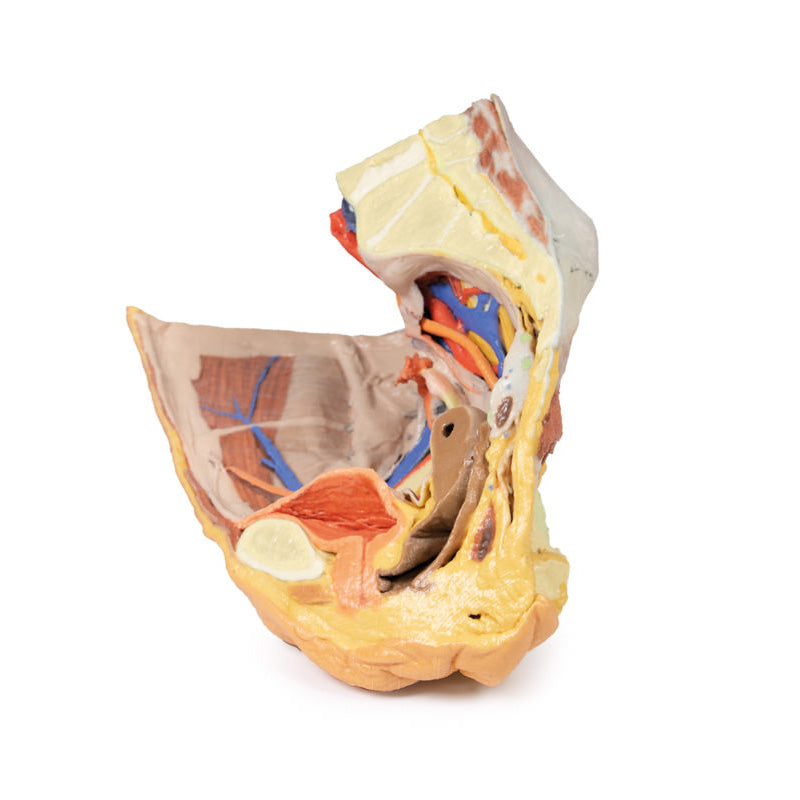

3D Printed Female right pelvis superficial and deep structures

The specimen has been sectioned transversely through the L4 vertebra, displaying a cross section of the colon, the epaxial musculature (psoas and quadratus lumborum muscles), and the abdominal wall musculature. The common iliac artery has been preserved from the level of the L4 vertebra, and its bifurcation into the external and internal iliac arteries can be observed at the level of the sacral promontory. Deep to the arteries the common iliac vein and the origin of the inferior vena cava are visible.

The external iliac artery and vein passes anteroinferiorly along the pelvic brim, giving rise to the inferior epigastric and deep circumflex arteries and veins before passing deep to the inguinal ligament. The psoas major muscle lies lateral to the external iliac artery, with the femoral nerve evident on its lateral margin close to the inguinal ligament. The lateral cutaneous nerve of the thigh travels laterally on the superficial surface of the iliacus muscle to exit the ‘false’ pelvis close to the anterior superior iliac spine.

Following the course of the internal iliac artery deep to the undissected peritoneum, many of the major branches of its anterior and posterior divisions can be identified. The anterior division divides (deep to the peritoneum) into the superior vesical, obturator and obliterated umbilical artery. With a course parallel to the obturator artery, the obturator nerve can be seen running over obturator internus before entering the obturator canal together with the obturator vein (nerve, artery, vein in that order from superior to inferior).

Branches of the posterior division of the internal iliac artery, iliolumbar, and several lateral sacral arteries, can be seen arising from the posterior aspect of the internal iliac just below the sacral promontory. Its terminal branch, the superior gluteal, usually passes posteriorly between the lumbosacral trunk and S1 nerve, but this is hidden from view. The internal iliac vein and its tributaries - the obturator veins, uterine vein, vesical veins, etc. can be seen lying internal to the nerves and muscles. The large S1 and S2 roots and the smaller S3 nerve root can be seen emerging from the sacral foramina to pass laterally where it is joined by the lumbosacral trunk (L4 and l5 roots) which is not visible, to form the sciatic nerve which exits through the greater sciatic foramen to emerge on the posterior aspect in the gluteal region. In the pelvis as these roots pass laterally they are interdigitated between the fibres of piriformis muscle.

The right ureter can be clearly seen as it passes inferiorly on the posterior abdominal wall superficial to psoas muscle. It passes over the pelvic brim at the bifurcation of the common iliac artery to descend on the lateral wall of the pelvis before passing medially in the base of the broad ligament (hidden from view as the peritoneal folds that ‘drape’ over the uterine [Fallopian] tubes are still intact) to reach the lateral angles of the bladder. In the pelvis the viscera which lies most anteriorly is the bladder. Its thick wall and cavity is easily seen in this mid-sagittal cut. Indeed the ureteric orifice can be seen at the angle of the trigone of the bladder on its internal mucosal surface. The relations of the uterus to the vagina are clearly visible in the mid-sagittal section. Indeed the anterior and posterior fornices are clearly seen as is the os of the cervix. The round ligament of the uterus has been removed along with some peritoneum to display the structures in the lateral pelvic wall. The entire right Fallopian tube is identifiable as it passes from the lateral aspect of the body of the uterus to terminate as the fimbria which overhangs the right ovary which is still held in place by its mesovarium. The ovary is attached laterally to the pelvic brim by the suspensory ligament of the ovary (sometimes called the infundibulopelvic ligament) which contains its named artery and veins. The ligament of the ovary is clearly visible leading from the medial aspect of the ovary to the lateral surface of the uterus.

There are only small cut surfaces of the rectum (visible as little islands of mucosa) visible on the sagittal cut surface suggesting that it is slightly off the midline plane. Some pararectal lymph nodes (coloured pale green) can be seen close to these islands of rectal mucosa. On the anterior aspect of the 3D print the inguinal ligament has been retained and deep to it the femoral artery, vein and nerve pass to the anterior compartment of the thigh.

In the gluteal region (note the femur has been removed to expose the acetabulum) the sciatic nerve can be seen emerging from the greater sciatic foramen (GSF) alongside the inferior gluteal vessels below the remains of the piriformis fibres, whereas the superior gluteal vessels and nerve emerges above the piriformis. Below these vessels the pudendal nerves and vessels can be seen exiting the GSF and passing over the sacrospinous ligament to enter the lesser sciatic foramen, thereby entering the perineum along the lateral wall of the ischioanal fossa.

3D Printed Female right pelvis superficial and deep structures

This 3D printed female right pelvis preserves both superficial and deep structures of the true and false pelves, as well as the inguinal ligament, the obturator membrane and canal, and both the greater and lesser sciatic foramina. Somewhat unique is the removal of portions of the peritoneum (a grayish colour) to create ‘windows’ displaying extraperitoneal structures.The specimen has been sectioned transversely through the L4 vertebra, displaying a cross section of the colon, the epaxial musculature (psoas and quadratus lumborum muscles), and the abdominal wall musculature. The common iliac artery has been preserved from the level of the L4 vertebra, and its bifurcation into the external and internal iliac arteries can be observed at the level of the sacral promontory. Deep to the arteries the common iliac vein and the origin of the inferior vena cava are visible.

The external iliac artery and vein passes anteroinferiorly along the pelvic brim, giving rise to the inferior epigastric and deep circumflex arteries and veins before passing deep to the inguinal ligament. The psoas major muscle lies lateral to the external iliac artery, with the femoral nerve evident on its lateral margin close to the inguinal ligament. The lateral cutaneous nerve of the thigh travels laterally on the superficial surface of the iliacus muscle to exit the ‘false’ pelvis close to the anterior superior iliac spine.

Following the course of the internal iliac artery deep to the undissected peritoneum, many of the major branches of its anterior and posterior divisions can be identified. The anterior division divides (deep to the peritoneum) into the superior vesical, obturator and obliterated umbilical artery. With a course parallel to the obturator artery, the obturator nerve can be seen running over obturator internus before entering the obturator canal together with the obturator vein (nerve, artery, vein in that order from superior to inferior).

Branches of the posterior division of the internal iliac artery, iliolumbar, and several lateral sacral arteries, can be seen arising from the posterior aspect of the internal iliac just below the sacral promontory. Its terminal branch, the superior gluteal, usually passes posteriorly between the lumbosacral trunk and S1 nerve, but this is hidden from view. The internal iliac vein and its tributaries - the obturator veins, uterine vein, vesical veins, etc. can be seen lying internal to the nerves and muscles. The large S1 and S2 roots and the smaller S3 nerve root can be seen emerging from the sacral foramina to pass laterally where it is joined by the lumbosacral trunk (L4 and l5 roots) which is not visible, to form the sciatic nerve which exits through the greater sciatic foramen to emerge on the posterior aspect in the gluteal region. In the pelvis as these roots pass laterally they are interdigitated between the fibres of piriformis muscle.

The right ureter can be clearly seen as it passes inferiorly on the posterior abdominal wall superficial to psoas muscle. It passes over the pelvic brim at the bifurcation of the common iliac artery to descend on the lateral wall of the pelvis before passing medially in the base of the broad ligament (hidden from view as the peritoneal folds that ‘drape’ over the uterine [Fallopian] tubes are still intact) to reach the lateral angles of the bladder. In the pelvis the viscera which lies most anteriorly is the bladder. Its thick wall and cavity is easily seen in this mid-sagittal cut. Indeed the ureteric orifice can be seen at the angle of the trigone of the bladder on its internal mucosal surface. The relations of the uterus to the vagina are clearly visible in the mid-sagittal section. Indeed the anterior and posterior fornices are clearly seen as is the os of the cervix. The round ligament of the uterus has been removed along with some peritoneum to display the structures in the lateral pelvic wall. The entire right Fallopian tube is identifiable as it passes from the lateral aspect of the body of the uterus to terminate as the fimbria which overhangs the right ovary which is still held in place by its mesovarium. The ovary is attached laterally to the pelvic brim by the suspensory ligament of the ovary (sometimes called the infundibulopelvic ligament) which contains its named artery and veins. The ligament of the ovary is clearly visible leading from the medial aspect of the ovary to the lateral surface of the uterus.

There are only small cut surfaces of the rectum (visible as little islands of mucosa) visible on the sagittal cut surface suggesting that it is slightly off the midline plane. Some pararectal lymph nodes (coloured pale green) can be seen close to these islands of rectal mucosa. On the anterior aspect of the 3D print the inguinal ligament has been retained and deep to it the femoral artery, vein and nerve pass to the anterior compartment of the thigh.

In the gluteal region (note the femur has been removed to expose the acetabulum) the sciatic nerve can be seen emerging from the greater sciatic foramen (GSF) alongside the inferior gluteal vessels below the remains of the piriformis fibres, whereas the superior gluteal vessels and nerve emerges above the piriformis. Below these vessels the pudendal nerves and vessels can be seen exiting the GSF and passing over the sacrospinous ligament to enter the lesser sciatic foramen, thereby entering the perineum along the lateral wall of the ischioanal fossa.